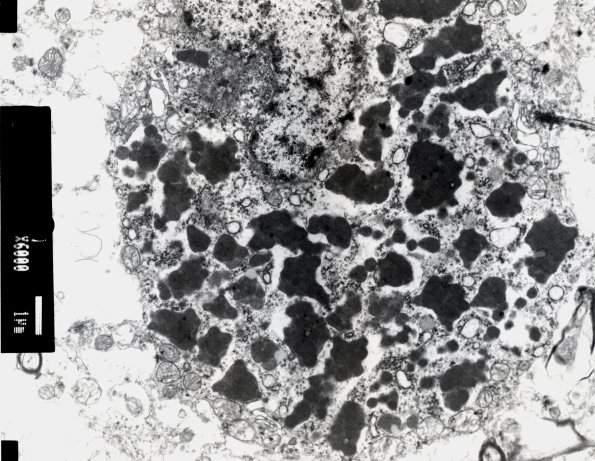

3E2 NCL (Case 3) EM 3

This cortical neuron contains a large amount of bland lipopigment. (electron micrographs)